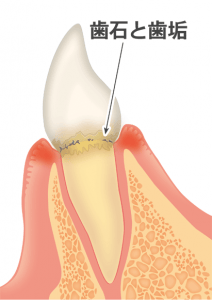

歯周病とは

歯周病菌や噛む力の影響で、歯茎が腫れたり、歯を支えている骨(歯槽骨)が溶けてしまう病気です。

歯周病が進むとどうなるか